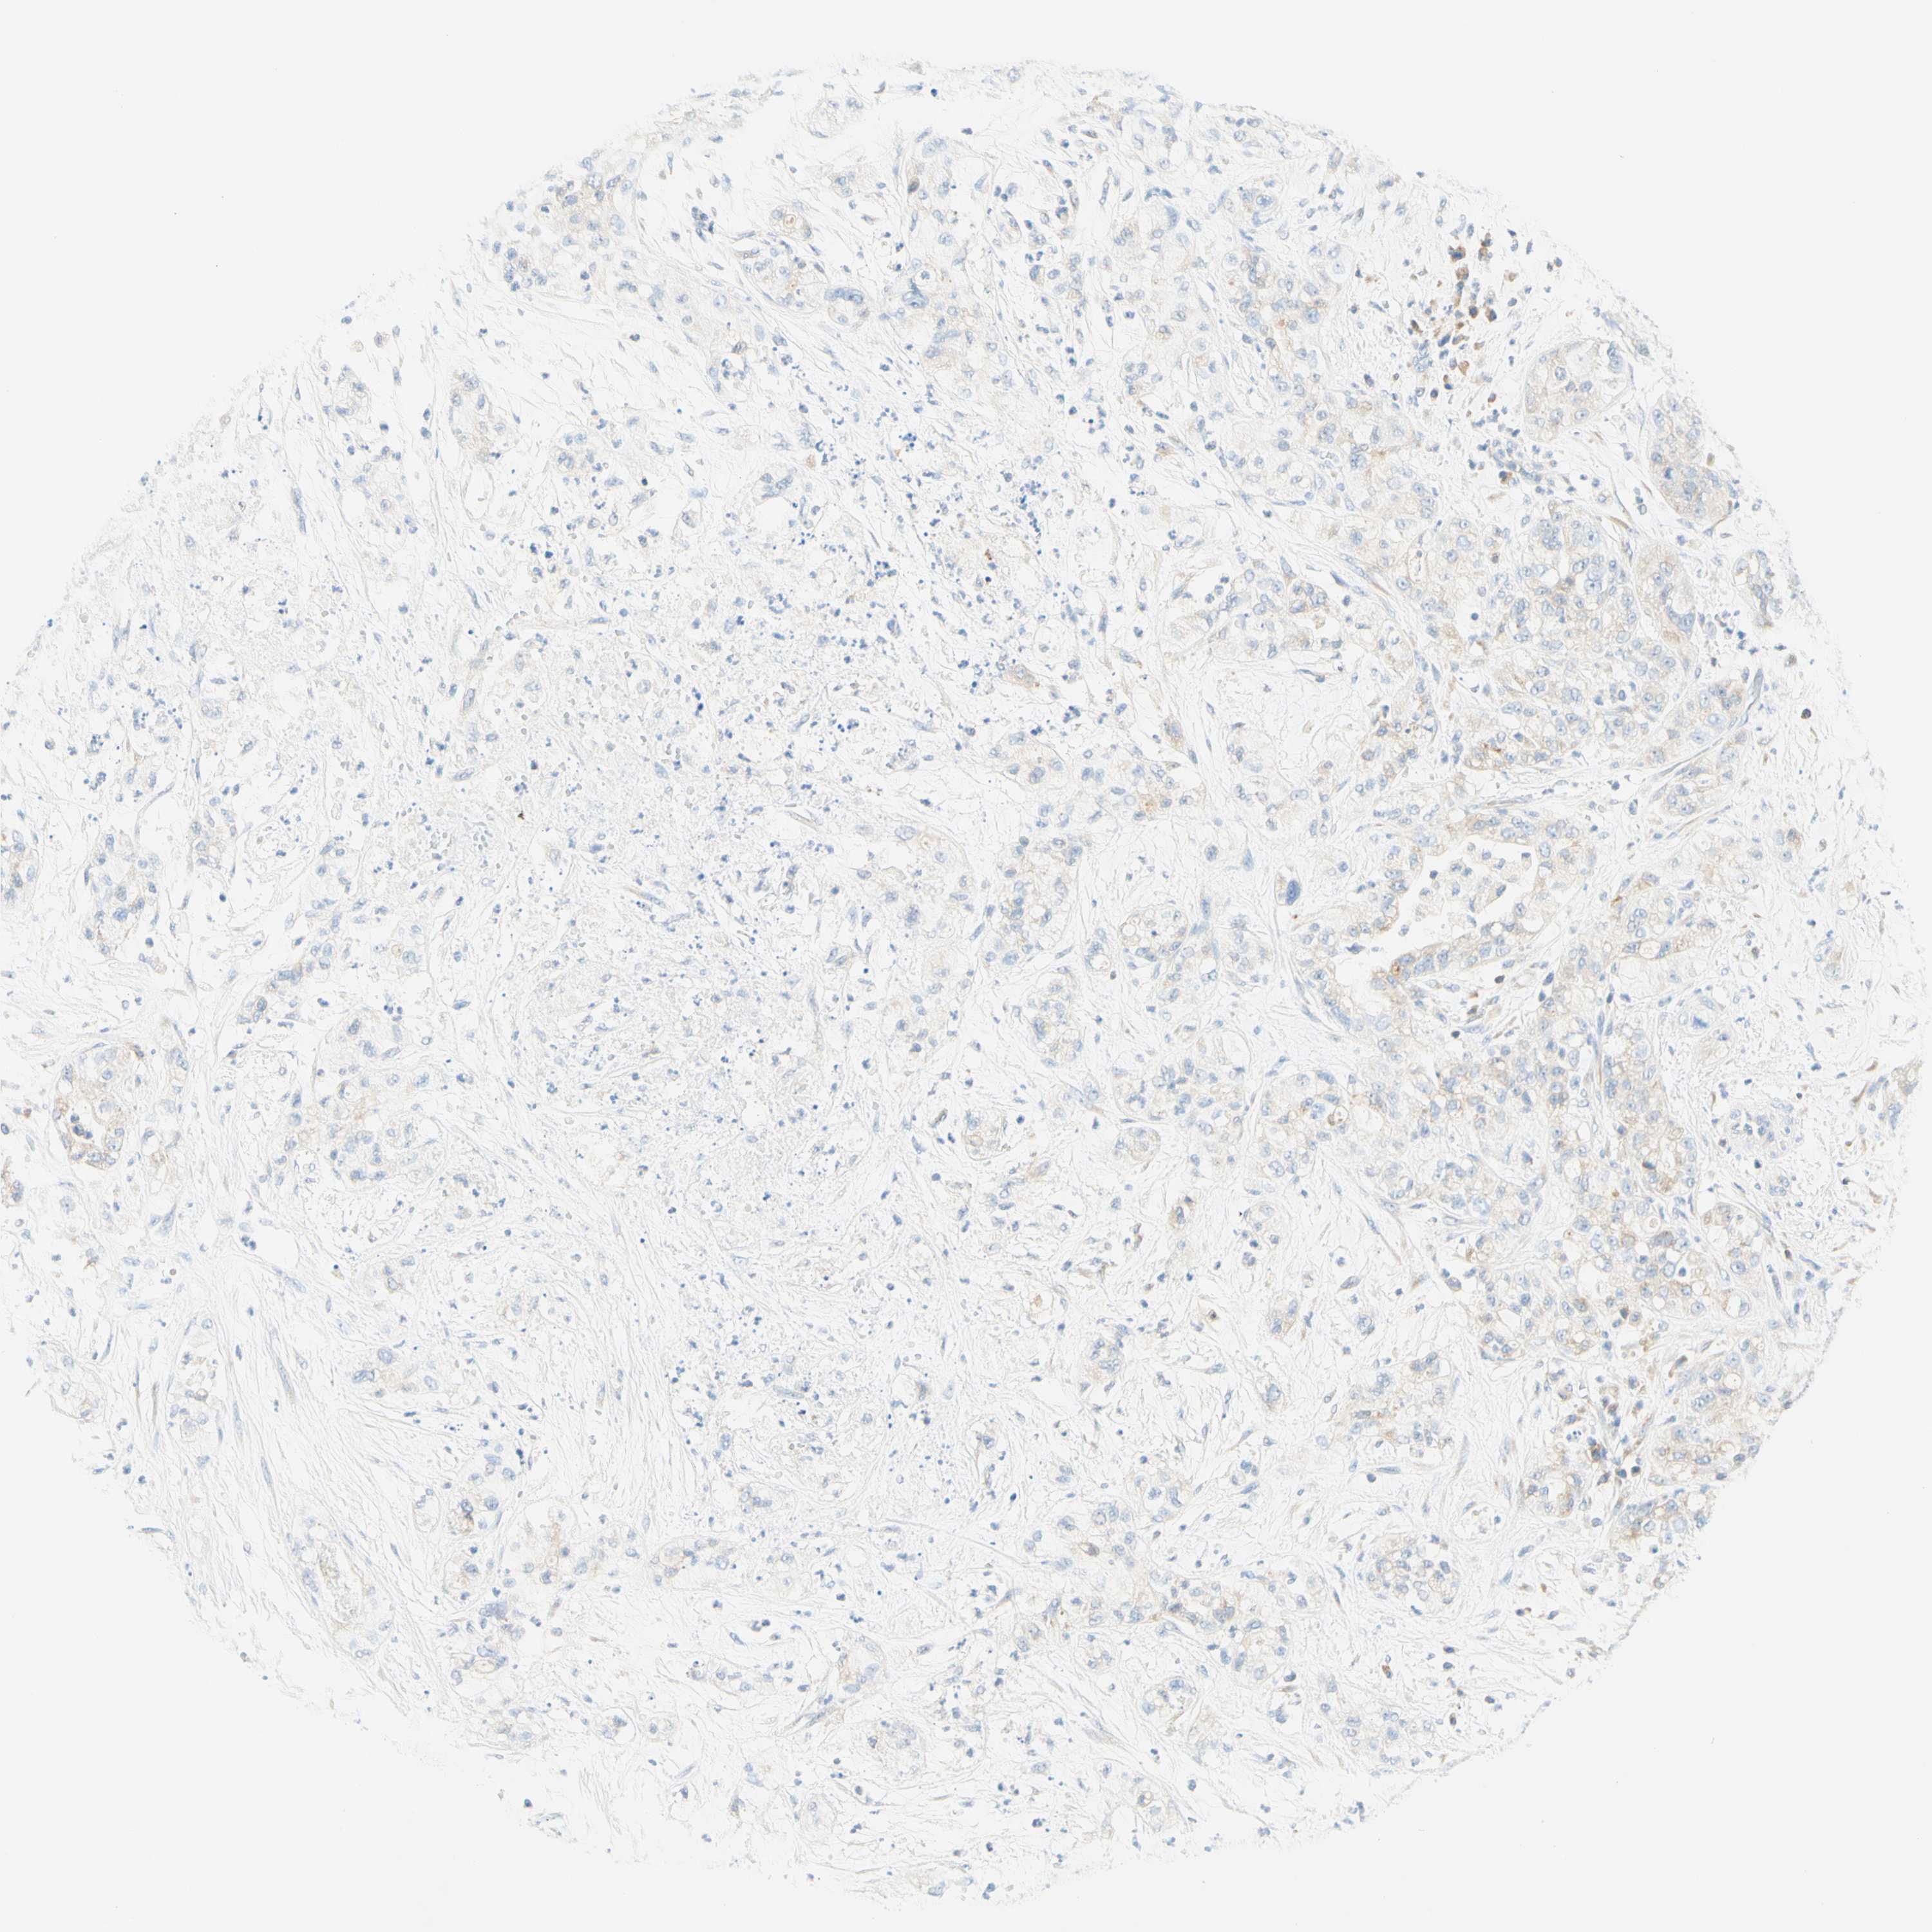

PANCREATIC CANCER - Protein expressioni

A mouse-over function shows sample information and annotation data. Click on an image to view it in a full screen mode. Samples can be filtered based on level of antibody staining by selecting one or several of the following categories: high, medium, low and not detected. The assay and annotation is described here.

Note that samples used for immunohistochemistry by the Human Protein Atlas do not correspond to samples in the TCGA dataset.

Antibody stainingi

Antibody staining in the annotated cell types in the current human tissue is reported as not detected, low, medium, or high, based on conventional immunohistochemistry profiling in selected tissues. This score is based on the combination of the staining intensity and fraction of stained cells.

Each image is clickable and will lead to virtual microscopy that enables deeper exploration of all samples and also displays staining intensity scores, fraction scores and subcellular localization as well as patient and tissue information for each sample.

Antibody HPA011157

Antibody CAB002223

Antibody CAB012978

Antibody CAB079960

Adenocarcinoma, NOS

Adenocarcinoma, metastatic, NOS